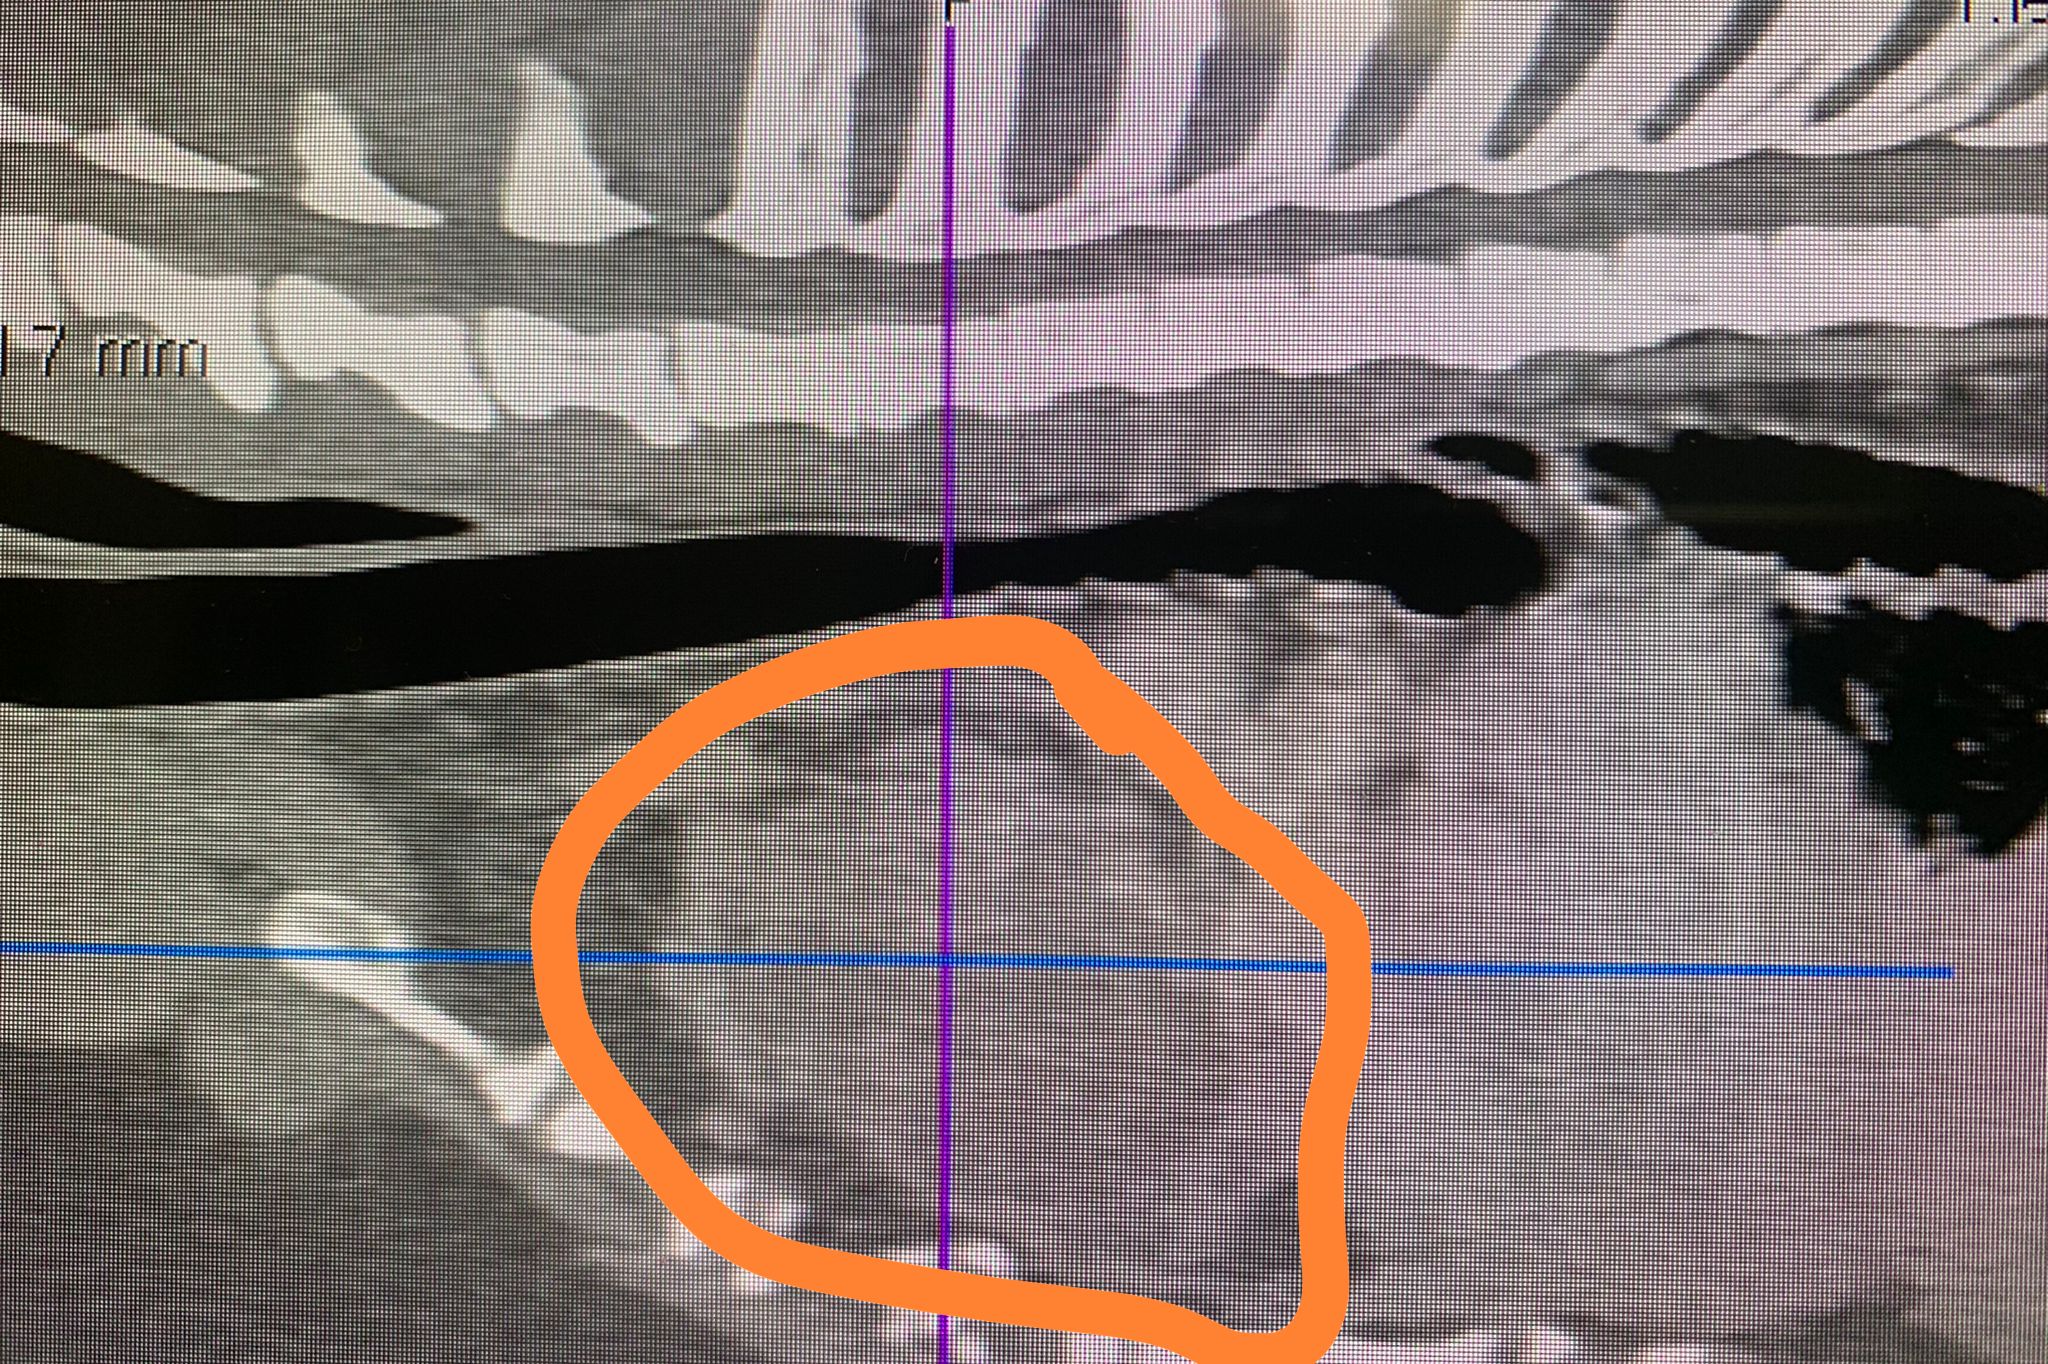

L’esame della tac, quanto mai provvidenziale in questi casi, ha velocemente evidenziato un tumore nel torace con un diametro di 20 centimetri. La biopsia ha rivelato con ulteriore precisione la sua natura di timoma. Un quadro che prevedeva per Romi una sola strada per sopravvivere: l’intervento chirurgico.

“Il tumore – spiega il veterinario Tomaso Piaia – aveva anche iniziato a sanguinare quindi abbiamo dovuto sottoporre Romi ad una trasfusione di sangue. L’accesso al tumore si è rivelato complicato ed invasivo costringendoci ad una sternotomia. In sostanza abbiamo dovuto aprire lo sterno. Isolare il timoma è stato poi il passaggio più complicato perché il tumore aveva sviluppato aderenze con un polmone e con il cuore.

Un intervento, dunque, abbastanza complesso ma alla fine tutto è filato per il verso giusto. Per qualche giorno abbiamo dovuto lasciare a Romi un drenaggio toracico per poter aspirare il sangue e l’aria residua. Oggi, però, possiamo sorridere nel vederlo tornare alla sua vita di sempre“.